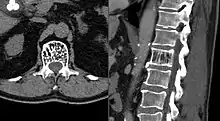

| Axial and sagittal CT views of a vertebral hemangioma | |

On computed tomography (CT) or radiograph, VHs can cause rarefaction with vertical striations (often referred to as corduroy pattern) or a coarse honeycomb appearance. A polka-dot appearance on CT scan represents a cross-section of reinforced trabeculae.[11][13] CT best defines the bony architecture and is the best diagnostic imaging method.[14]